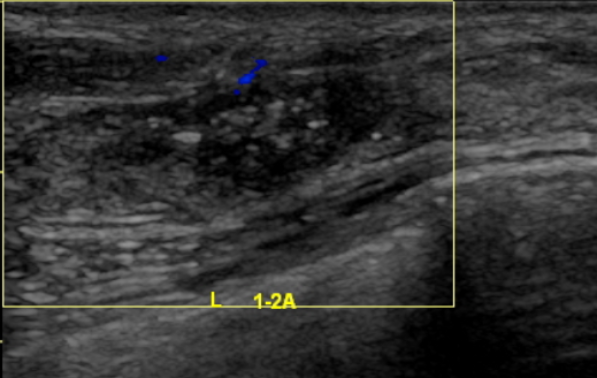

2021.9.9乳腺B超提示:左侧乳腺1-2点钟A环内见大小约18*15*6mm低回声区,边界不清,内见散在强光点,周边可见血流信号。余双侧乳腺腺体形态、结构未见异常。

两侧腋窝可见多枚低回声结节,边界清,有包膜,左侧较大者约9*5mm,右侧较大者约10*4mm,血流信号不明显。

影像诊断:左侧乳腺低回声区(BI-RADS:6类);两侧腋窝多枚淋巴结显示。

图4.乳腺B超(2021-9-9)